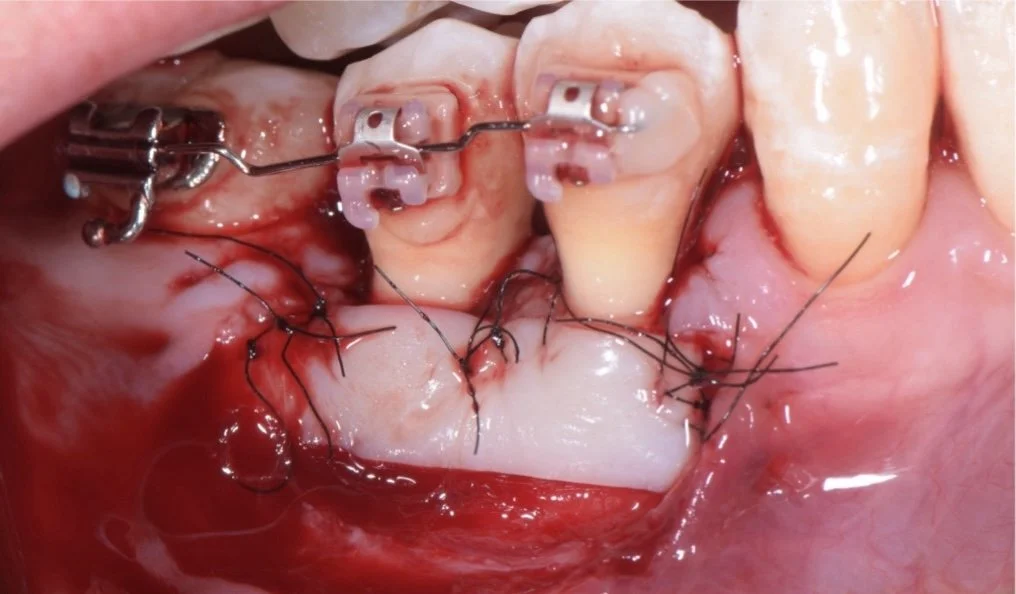

Apprentissage pratique intensifLa pratique à quatre mains directement au cabinet avec un formateur permet d'acquérir des gestes précis et de perfectionner sa technique dans un cadre réel. Cette immersion favorise une montée en compétence rapide et efficace.